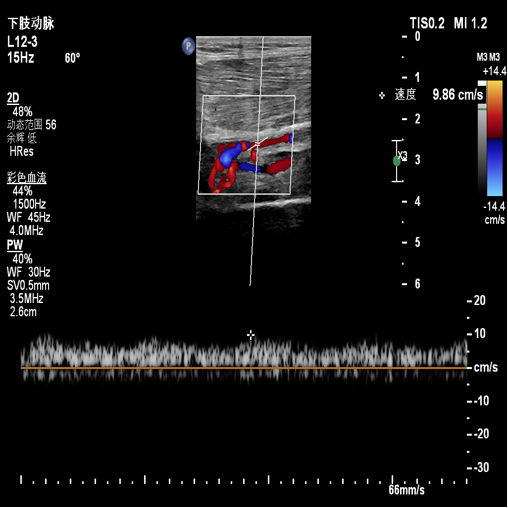

术前超声评估:提示腘动脉血栓。

图:胫腓干血栓及直径

胫后及腓动脉起始处彩色血流图

图:术前超声